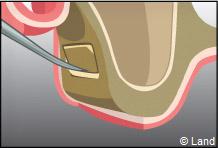

Une fenêtre est délimitée et réclinée à l’intérieur du sinus de manière à aménager un espace. Cet espace est rempli par le matériau de comblement qui peut être recouvert par une membrane.

Actuellement, tous les biomatériaux peuvent être utilisés pour les comblements sinusiens.